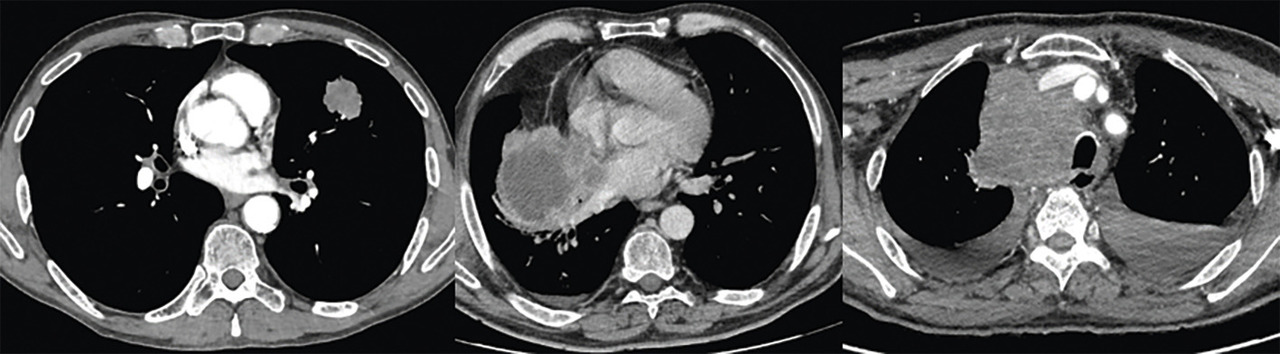

L’aspect radiologique de la lésion primitive oriente le diagnostic, bien que non spécifique : les CBPC se manifestent le plus souvent comme d’énormes complexes ganglio-tumoraux médiastinaux, les carcinomes épidermoïdes sont généralement situés au niveau des bronches proximales avec atélectasie d’aval, nécrose ou cavitation centrale ; enfin, les adénocarcinomes se caractérisent par des lésions périphériques (figure).